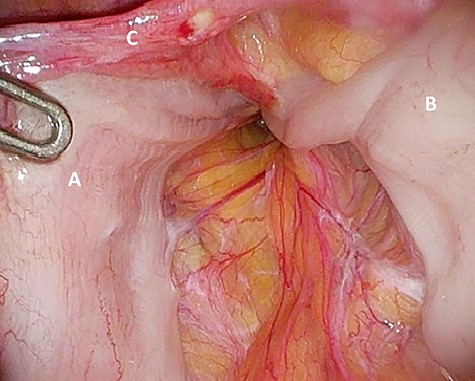

Preperitoneal view of the large hernia sac (A) ‘hidden’ in the scar tissue.

The patient agreed to proceed with diagnostic laparoscopy for a re-re-repair of the left inguinal hernia. Intraoperatively, a loop of the sigmoid colon, which previously was hidden by colonic adhesions, was fixed into a hernia orifice lateral–caudal of the preperitoneal mesh (Fig. 4). After reopening of the peritoneum and removal of the mesh, extensive preperitoneal preparation revealed the hernia orifice located in dense scar tissue not being dissected previously (Fig. 5). A new mesh (BARD® 3D Light Mesh 12 × 17 cm) was inserted and fixed medially at the Cooper’s ligament.